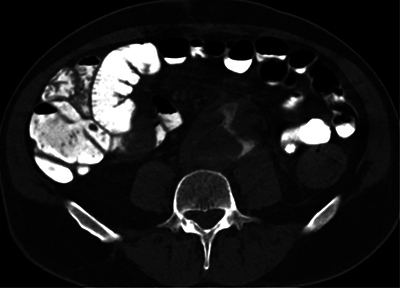

Aortoenteric Fistula with Digestive Contrast Material Leaking in the Aneurysmal Sac.

Teaching point: Aortoenteric fistula, a major complication of aortic surgery, can be identified with certainty on CT scan with opacification of the intestinal tract.